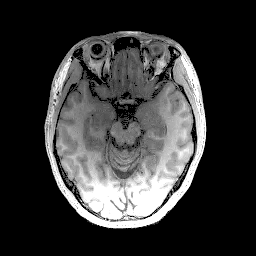

In the second set of evaluations, we considered regularization-based denoising of a 230180 single-channel T1-weighted MR image, obtained by applying complex coil-combination to an 8-channel dataset and subsequently adding simulated complex Gaussian noise. The ground truth and noisy images are shown in Fig. 3.

For reconstruction, the matrix was an identity matrix. Following Refs. [24, 10, 25, 28], the magnitude was regularized using a Huber-function penalty as given by Eq. (28), where a finite difference transformation was used to enforce spatial smoothness of the image. Following Ref. [10, 2, 4, 5, 7], the phase was regularized using a Tikhonov penalty as given by Eq. (29), also using a finite difference transformation to enforce spatial smoothness. All algorithms were initialized with the noisy image.